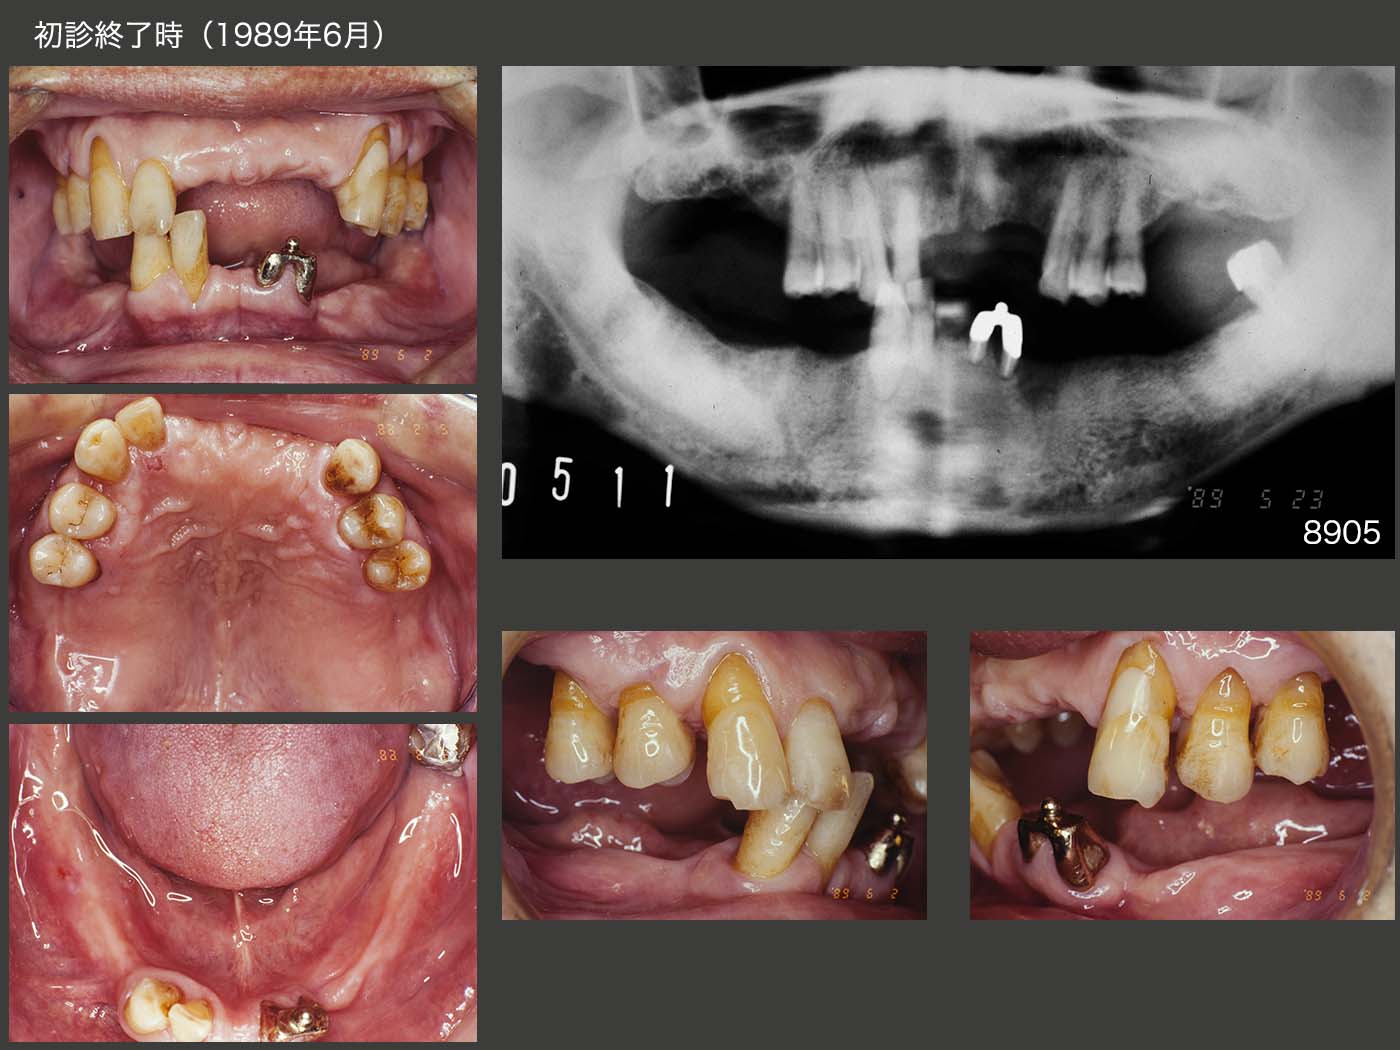

1988年4月初診,51歳男性.主訴は,左下3の歯肉が腫れた.右上6,左上6,7,左下3および右下6,7の歯周ポケットは10mm以上あり,当時の私の実力では保存不可能であった.特に,右側の上下6を抜去したため,臼歯部の咬合支持がなくなり,下顎位は右側の上下2,3で保持されていた.と言っても,当時の私は咬合支持と言う概念はなく,この後下顎位を全く無視した治療を行ってしまった.

保存不可能な歯の抜去後,上下に暫間義歯を装着した.この時は右側の上下2,3が咬合しており下顎位は正しいと思われる.

1989年6月,初診終了時の状態.左下2の近心に6mmの歯周ポケットが存在したが,ここ以外は5mm以内に収まった.アタッチメントはBona 604Aを用いた.なお,根面板を連結固定してアタッチメントを付与した症例は,後にも先にもこのケース1例だけである.

初診終了時の義歯を装着した状態.左下の根面アタッチメントの支台歯辺縁歯肉を開放し,唾液による自浄性の向上を図った.